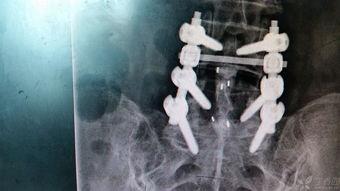

3. 植入钉棒:医生会通过切口,将特制的钉子和棒子植入到腰椎上。这些钉子和棒子就像一把把“锁”,能够牢牢地固定住骨折的部位。

4. 固定:在钉子和棒子植入后,医生会调整它们的位置,确保腰椎的稳定性。